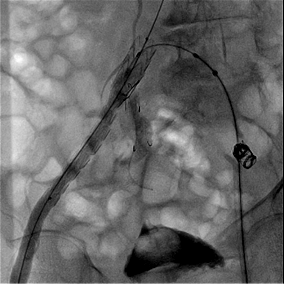

在手术中,瘤区巨大、血管扭曲、器械推送和狭窄血管支架通过等都是对主刀医生的考验,和临床打交道二十多年的张波,熟稔地操作器具,看准时机,把握进退;榫卯相接,严丝合缝,卡点恰到好处。2个多小时的手术,仅在双侧股动脉各留一个黄豆大小穿刺口,成功拆除腹主动脉瘤及双髂动脉瘤,同时重建了右侧髂内动脉。

术中行右侧髂内动脉IBD及腹主动脉-双侧髂动脉瘤支架隔绝